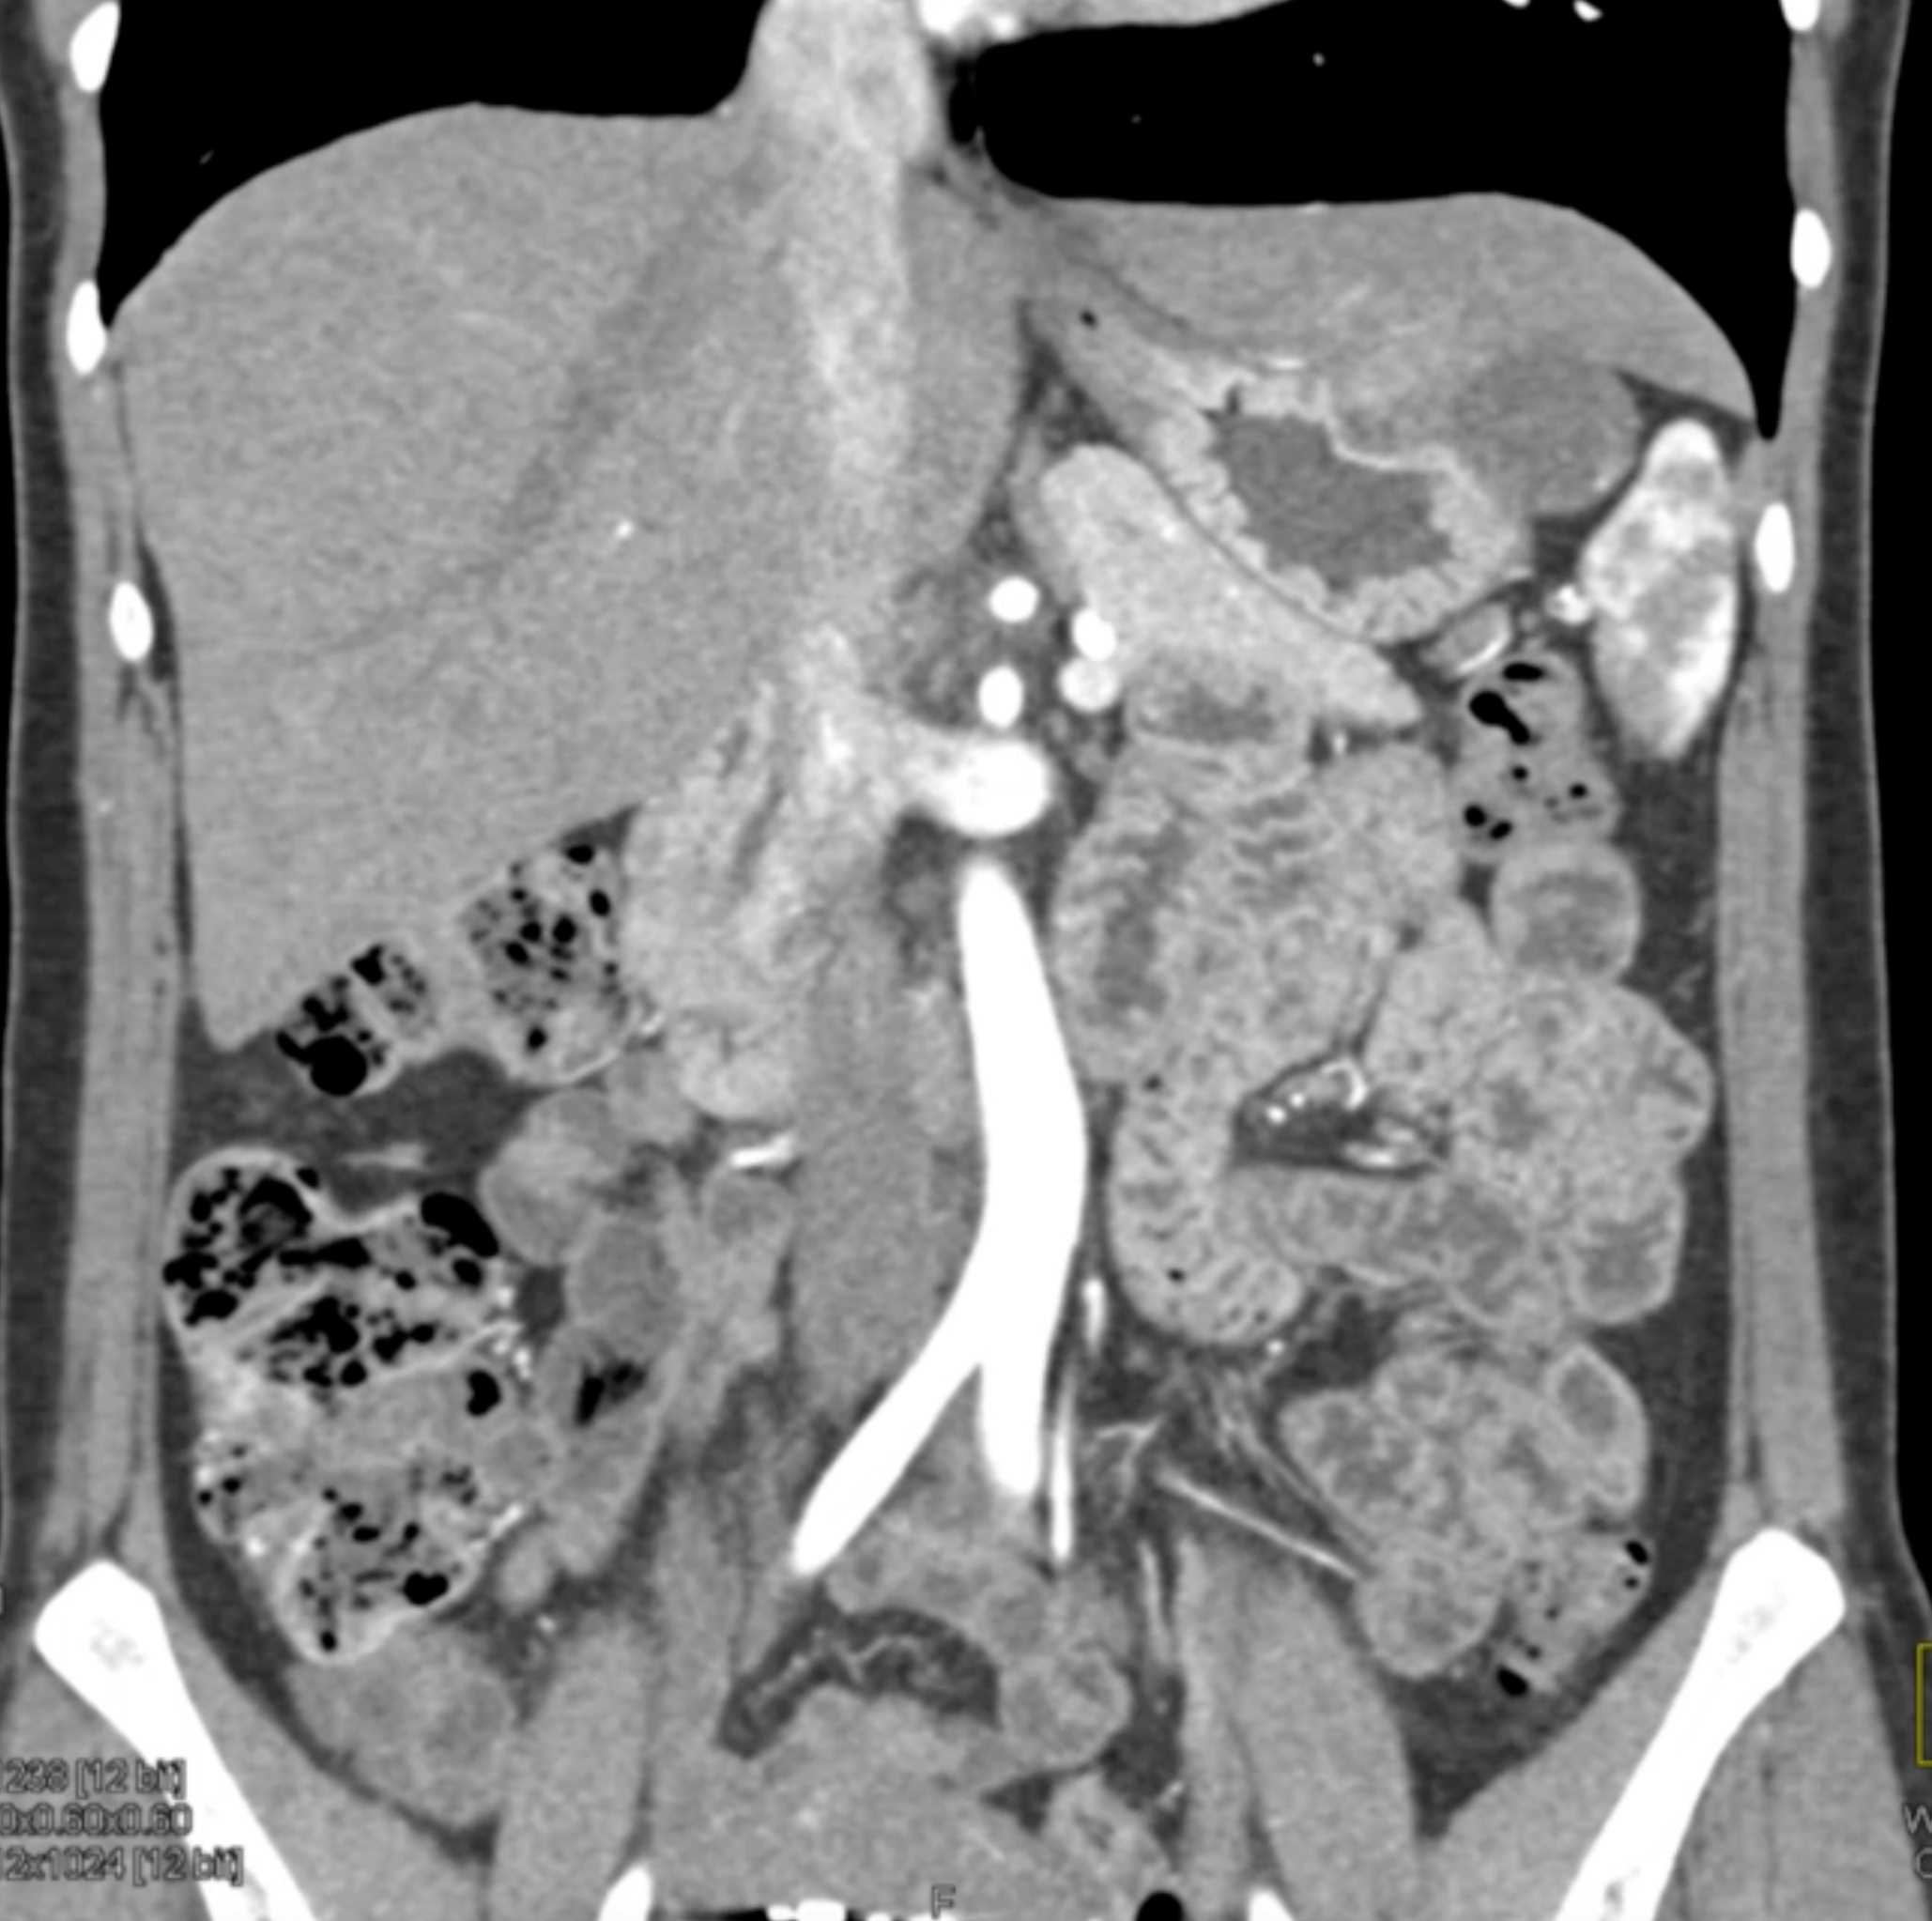

Multiple Gastric GIST Tumors with Spread to Nodes (Carney-Stratakis Syndrome)